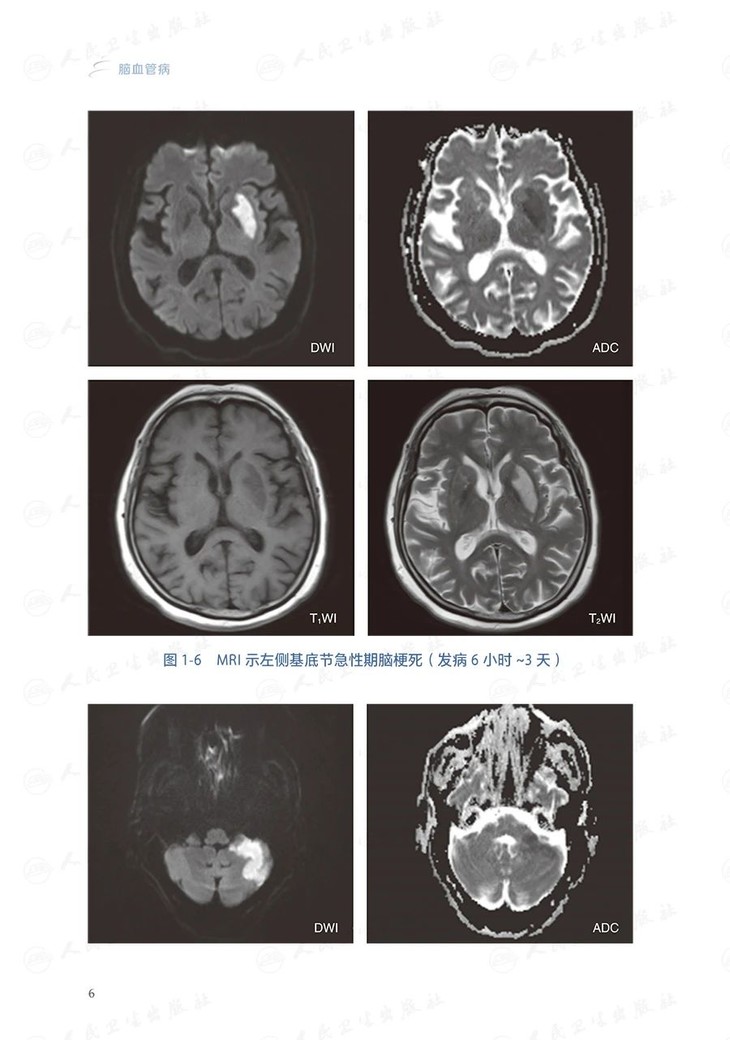

本分册共分12章,包括缺血性卒中、短暂性脑缺血发作、自发性颅内出血、蛛网膜下腔出血、 脑血管狭窄/闭塞、动脉瘤 、烟雾病、脑血管畸形、脑动静脉瘘、脑小血管病以及少见病因脑血管病。每个病种的撰写内容包括: 概述(包括定义和流行病学,简介病因与发病机制)、 临床表现、 辅助检查 (包括影像学检查等)、 诊断和鉴别诊断、治疗( 包括治疗前评估, 治疗方式选择, 治疗管理)以及预后评估及随访管理。对于从事神经系统疾病诊疗、教学及研究工作的神经内科、神经外科、神经介入科、急诊科、老年科等相关专业的医生、学生及研究人员具有较强的指导价值。